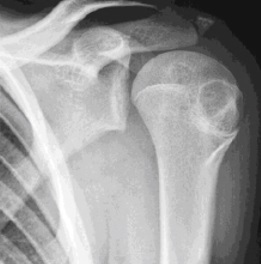

5

Q

Qual diagnóstico?

A

Projeção óssea com cortical contínua

Dx: Osteocondroma